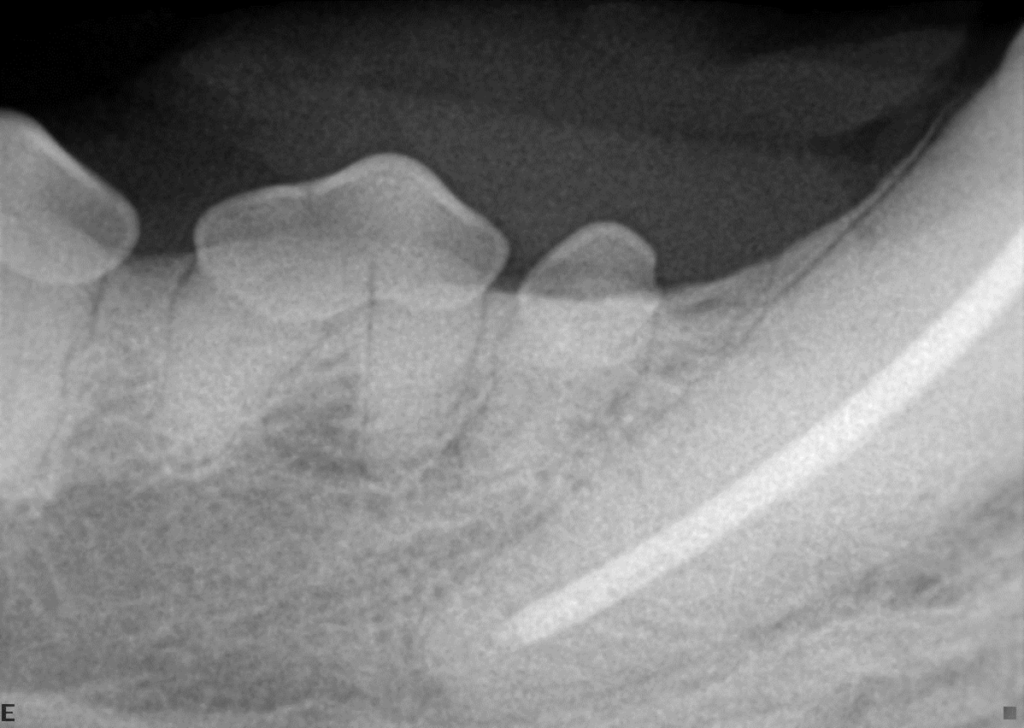

Broken teeth need to be treated immediately.  A tooth that has been broken less than 48 hrs can be saved with a procedure called a “Vital Pulpotomy.”   After 48 hrs., treatment options are root canal therapy or extraction.  Since our pet friends rely heavily on their teeth, saving them is a better and less painful option (root canal therapy).   Leaving a broken tooth in the mouth without treatment causes unnecessary, prolonged oral pain. Finally, a discolored tooth is a dead tooth.  A recent study indicated that 92% of all discolored teeth are non-vital (dead).  Saving those teeth via root canal therapy +/- a crown is highly recommended for those teeth that are deemed strategic (all canine teeth, maxillary 4th premolars and mandibular 1st molar teeth)